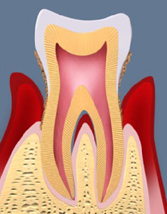

口腔内の汚れや歯垢が石灰化して歯石に変わると、歯と歯肉の間にある歯周ポケットと呼ばれる溝が深くなります。そこが細菌の温床となって歯周病菌の繁殖が進むと、歯肉が炎症を起こします。さらに炎症が進んで歯周ポケットの奥深くにまで広がると、歯根膜や歯槽骨までが菌によって溶かされ、歯を支えきれなくなり、最終的には歯を失ってしまいます。

歯肉炎

歯と歯ぐきの間にある溝にプラーク(歯垢)が溜まり、歯ぐきに炎症を起こします。プラークと炎症によって歯周ポケットができますが、この段階ではまだ、歯を支える歯槽骨は悪くなっていません。

軽度歯周炎

歯肉炎が進行した状態です。3~4mm程度となった歯周ポケット内にプラークや歯石が溜まって炎症が強くなるため、歯ぐきの色が赤みを帯びてきます。歯を支える歯槽骨も吸収を始めます。

中等度歯周炎

炎症が進行して歯周ポケットが4~6mm程度まで深くなった状態です。歯を支える歯槽骨の吸収も進行し、指で押すと歯がグラつく感じもあります。この程度まで進行すると、自覚症状(歯ぐきの腫れや出血)が現れます。

重度歯周炎

さらに歯肉炎が進行し、定期的に歯ぐきが腫れ、強い痛みが現れる状態です。